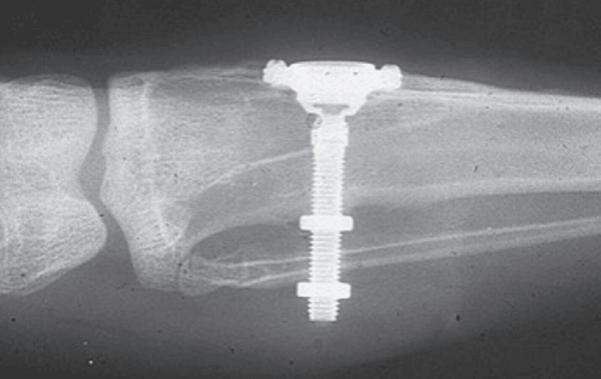

Ruim vijftig jaar geleden is het begrip osseointegratie geïntroduceerd door Per Ingmar Brånemark. Hij was een Zweedse arts die onderzoek deed naar botfysiologie. Door middel van het plaatsen van holle titanium buisjes in het femur van konijnen deed hij onderzoek naar de microcirculatie in het beenmerg en de genezing van botweefsel (afbeelding 1).

Omdat deze holle titanium buisjes werden gemaakt door een instrumentmaker en duur waren, besloot Brånemark deze na opoffering van de konijnen te hergebruiken. Zoals vaker bij onderzoek gebeurde, was de toevalsbevinding dat de holle titanium buisjes geïntegreerd waren in het bot. Hierna richtte zijn onderzoek zich vooral op deze verbinding, die later osseointegratie werd genoemd. Men wist al langer dat titanium inert reageert in het lichaam. In de jaren zestig werd het omhulsel van pacemakers, dat in eerste instantie van epoxiehars werd gemaakt, vervangen door titanium.

In Amsterdam werden vooral de Brånemark-implantaten geplaatst. Ook hier moest op voorhand een cursus worden gevolgd in Zweden; anders mocht je de implantaten niet kopen (afbeelding 3).

In eerste instantie werden de implantaten gebruikt als ondersteuning voor overkappingsprothesen of voor de zogenaamde vaste Brånemarkbrug (afbeel-

ding 4). Esthetiek speelde in die tijd eigenlijk geen rol. Het ging voornamelijk over het functioneel maken van het gebit bij mensen waarbij, door verlies van elementen en steunweefsel, geen mogelijkheid meer was om een behoorlijke prothese te maken. De eerste implantaten hadden een glad (machined) oppervlak en werden in twee fasen geplaatst. Bij het Brånemark-protocol werd het implantaat in het kaakbot geplaatst, waarbij de gingiva altijd werd gesloten. Na zes maanden werd het implantaat opgezocht, waarbij er direct een steriel abutment op werd geplaatst. De hoogte van het abutment werd afgestemd op de hoogte van de gingiva ter plaatse. Vervolgens werd de suprastructuur op abutmentniveau afgedrukt.